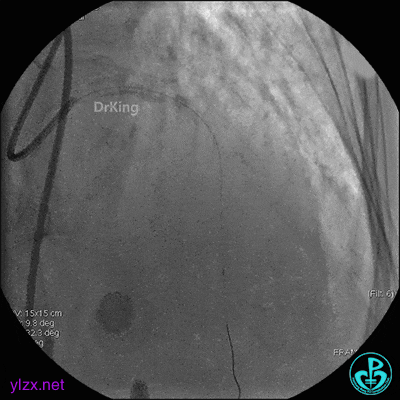

1周后复查造影,见粗大前降支3级血流,近端严重狭窄伴管壁严重钙化影,病变累及前降支开口。

球囊扩张后前降支中段植入支架。

前降支近端串联植入支架,前降支开口支架精确定位。

支架内非顺应性球囊后扩张。